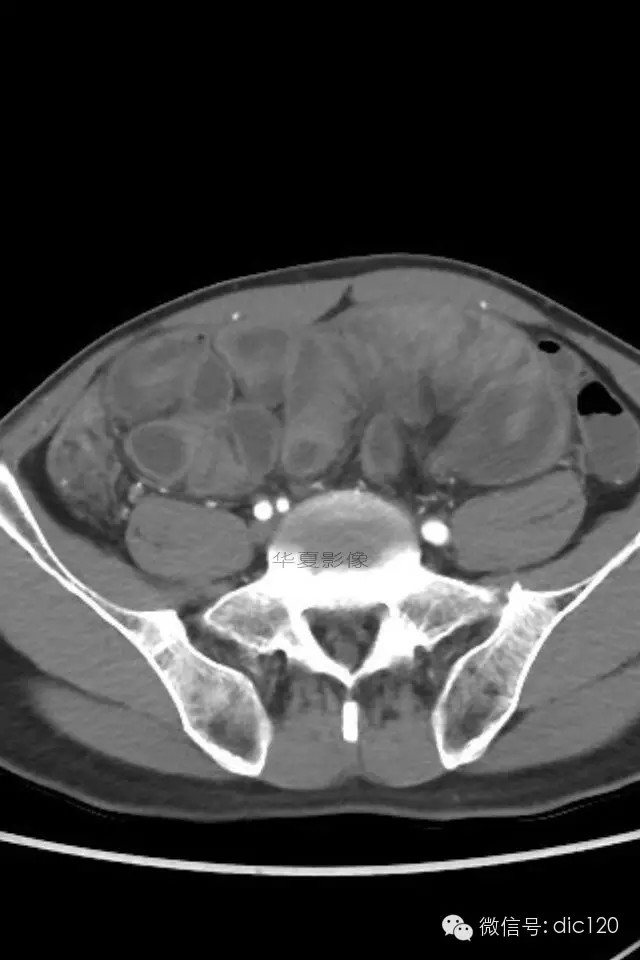

小肠禁锢症/腹茧症

肠茧症,即小肠茧状包裹症,又名:腹茧症,先天性小肠禁锢症。多为先天性畸形。

腹茧症以小肠被茧状包裹在一层异常的纤维膜内为其特征,为一种少见的,原因不明的特殊类型的肠梗阻。包膜厚薄不均,增厚处呈乳白色,包膜内小肠间或包膜间可有疏松粘连,包膜可局部增厚,形成缩窄环或束带压迫肠管形成梗阻,肠梗阻发生率约为57%,腹茧症伴腹腔内畸形率较高,约为54%。腹茧症92%的病人以肠梗阻就医,其中亚急性肠梗阻和慢性肠梗阻占71%,一些病人是在腹部手术时偶然发现本病。腹茧症女性多见,Francis总结以下情况可想到本病:1.青年女性,有不明原因的肠梗阻。2.既往又类似发作史,可自行缓解。3.常表现为腹痛及呕吐,但缺乏肠梗阻的四大典型症状。4.触诊腹部有无压痛的包块,质地软。腹茧症治疗以手术为主,充分松解粘连缩窄环,彻底解除梗阻使小肠复位或加以肠排列等。绝大多数病人术后症状消失,少数病人遗留症状,可试服用泼尼松,维生素B1治疗。

肠茧症分为两种类型:

1.单层包裹型 由单层纤维组织膜将小肠或其它脏器包裹。此种类型常包裹小肠及其系膜。手术时进腹容易,容易发生肠梗阻。

2.多层包裹型 俗称“千层饼”样包裹,其纤维层次多而广泛。手术时进腹困难,被包裹的脏器无移动性,发生肠梗阻的机会少。